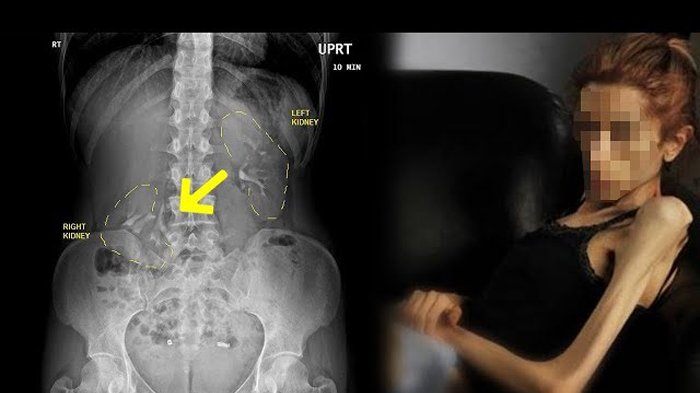

Astaga! Ginjal Wanita Ini Melorot Turun ke Panggul, Terlalu Kurus?

Wanita berusia 28 tahun mengalami ginjal melorot ke panggul setiap kali ia berdiri hingga merasakan kesakitan di perut kanannya selama enam tahun

TRIBUNMANADO.CO.ID - Seorang wanita berusia 28 tahun mengalami keanehan di organ tubuhnya, ginjalnya melorot ke panggul setiap kali ia berdiri.

Awalnya selama enam tahun terakhir ia merasakan kesakitan di perut kanannya, sangat menyiksa ketika ia berdiri.

Ia mengaku seperti ada benda yang terjatuh di dalam perutnya.

Saat ia memeriksakan kondisinya tersebut, ternyata dokter memberitahu bahwa organ yang bergerak itu adalah ginjalnya.

Dilansir dari Livescience, dalam dunia medis keadaan ini disebut dengan nephroptosis, kondisi dimana salah satu ginjal jatuh ke panggul ketika seseorang berdiri.

Menurut ahli urologi, Dr Akshay Sood mengatakan bahwa ini merupakan kondisi langka, yang bisa disebabkan karena seseorang kekurangan lemak yang menopang ginjal di dalam perut.

Ginjal memiliki banyak lemak di sekitarnya yang berguna untuk menopang posisinya agar stabil.

Terkadang untuk wanita yang kurus, ia tak memiliki cukup banyak lemak untuk menjaga ginjal agar tetap pada posisinya.

Sehingga ketika berdiri, ginjal tersebut bergerak turun ke panggul karena gravitasi.

Hal ini bisa berbahaya, karena ketika ginjal turun menyebabkan pembuluh darah dan saluran kencing atau ureter bengkok dan tersumbat.

Akibatnya bisa membuat ginjal membengkak lantaran air seni menumpuk.

Wanita asal Michigan ini akhirnya menjalani prosedur operasi untuk mengikat ginjal agar tetap stabil berada di posisinya.